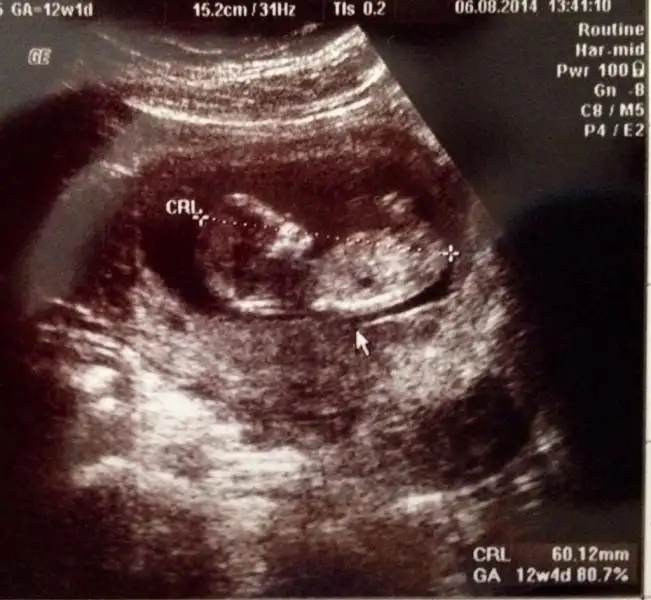

Aslında daha önce sormuştum ama tek bir arkadaş yorum yazdı belki farklı görüşler olur diye tekrar fikir almak istedim :) burda 12+1 iz normalde ama 3 gün önden gidiyoruz 12+4 görünüyor o yüzden minnağım :)

eger o çıkıntı ayak değilse erkek gibi duruyorKIZLAR SİZCE BENİMKİ NE